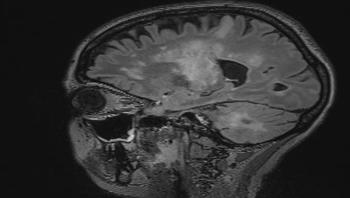

Researchers from the University of Zurich and the University Hospital Zurich reveal possible new treatment methods for a rare, usually fatal brain disease. Thanks to their discovery that specific antibodies play a key role in combating the viral infection, a vaccine against the disease progressive multifocal leukoencephalopathy could now be developed.